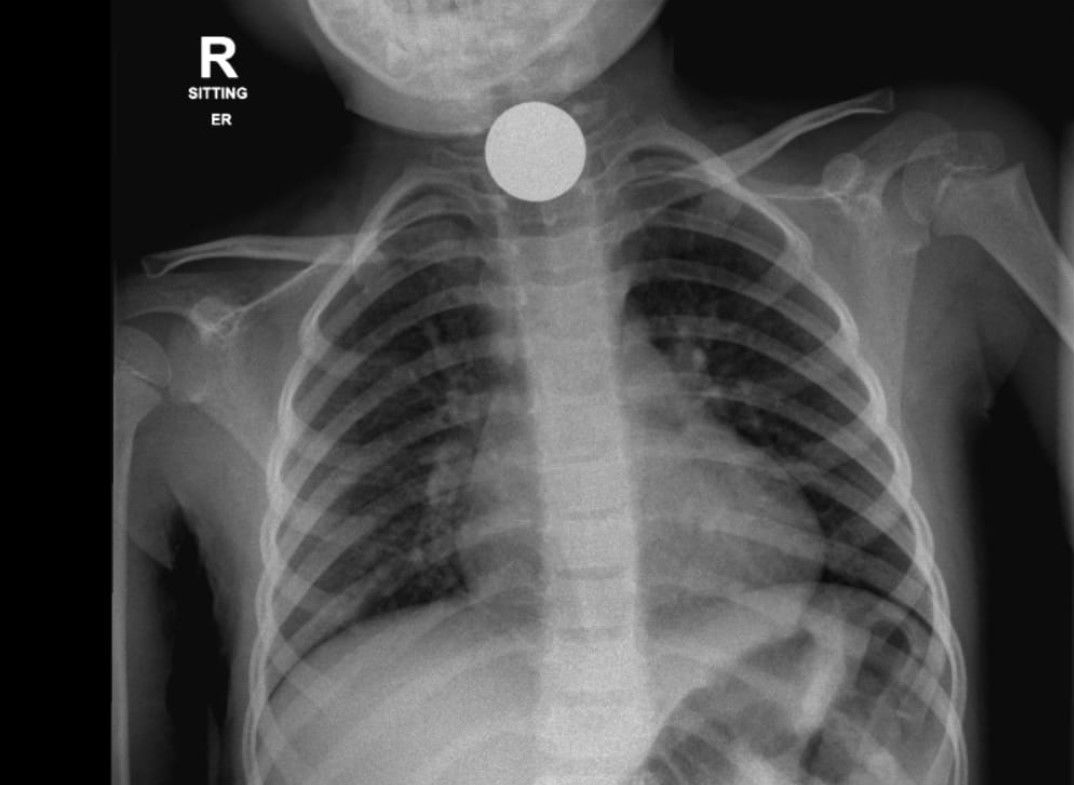

במקרה השני בילדה בת 4, בצילום נראה כי בלעה מטבעות כסף שנתקעו בוושט, באופן שדחק את קנה הנשימה והפריע לה לנשום בצורה תקינה, גם במקרה זה, לאחר התייעצות עם רופאים בכירים ומומחי אא"ג הוחלט כי על הילדה לעבור ניתוח על מנת להוציא את המטבעות מגופה. גם במקרה זה הפרוצדורה עברה בהצלחה. שני הילדות הושארו להשגחה רפואית במחלקת הילדים של בית החולים.